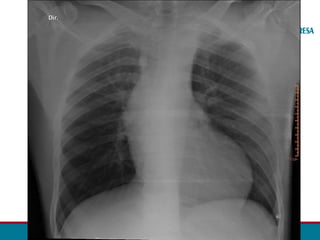

RADIOGRAFIA TORÁCICA

• Sinal de Roesler:

• Erosões bilaterais na borda inferior dos arcos costais (3ª - 9ª).

• Sinal do “ 3 invertido”

• Dilatação Subclávia E.

• Segmento estenótico aparece como um entalhe

• Dilatação pós estenótica.

• Contorno do arco aórtico apagado.

• Dilatação das artérias torácicas internas podem ser vistas

no perfil como densidade de partes moles.

• Aumento do Ventrículo Esquerdo

• Ápice cardíaco se projeta inferiormente e lateralmente à E

• Abaulamento margem cardíaca

• Sinal de Hoffman Rigler positivo